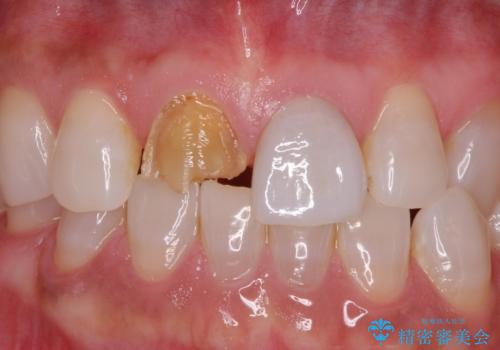

銀の詰め物を除去した後、その奥にある古い詰め物も除去し完全にむし歯を取り切ったことを確認してからセラミッククラウンを装着していきます。

詰め物の除去後、残った歯が薄い場合は今後の破折リスクを考慮して被せ物での修復処置を提案することがあります。